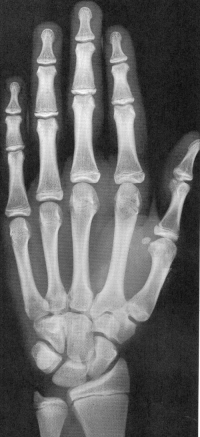

Sexo Feminino

10 anos

11 anos